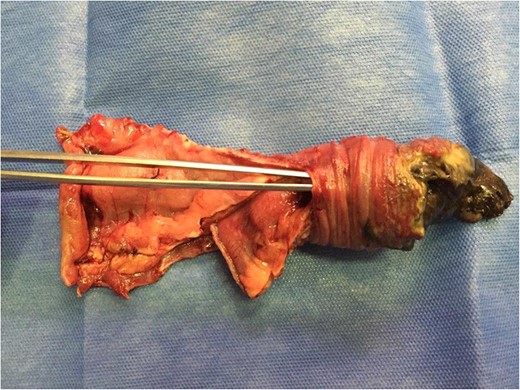

Not managing to reduce the invagination using blunt manual techniques, we performed a mini-laparotomy. Once the enterotomy was done and the invaginated segment was reduced, we observed necrotic intussuscepted mucosa, performing a resection and termino-terminal jejunojejunal anastomosis at 4 cm from the foot of the Roux-in-Y (Fig. 2). Upon finalizing the procedure, we once again confirmed fetal vitality (FCF: 140 bpm).

The dissection tweezers show the invaginated bowel segment. On the far right, an area of necrosis is seen with fibrine greenish streaks.